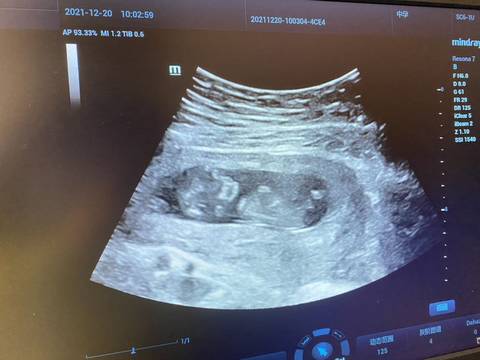

这是11周做的b超,能看出来男孩女孩吗

看不出来,这个普通人是很难直接判断男孩还是女孩的哦,其实只要孩子健健康康就好,生下来才最准

你好,对于宝宝是男孩女孩虽然很好奇,但是怀孕的单子、数据、表现是判断不出来的,在这也愿你心想事成。

你好。我们是判断不了男宝宝跟女宝宝的,孕期定期检查,我觉得宝宝健康就好的。祝心想事成 。

太心急了些吧,十一周宝宝各项都没发育好呢吧